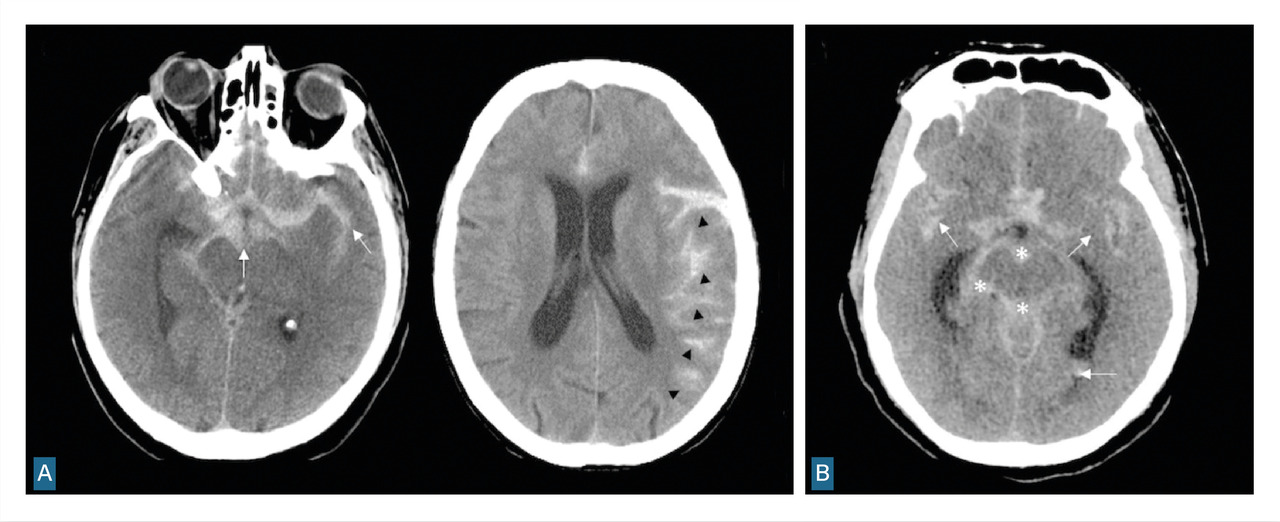

L’angiographie digitale permet de planifier et de suivre le traitement lorsqu’il est réalisé par voie endovasculaire. (fig. 4)